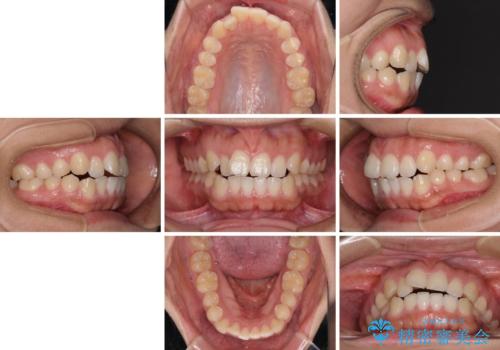

- 20代女性

- メタルブラケット

- 3年1ヶ月

- 口が閉じにくさを気にして来院された患者様です。

上下の前歯が前方に突出していたため、上下左右の第一小臼歯4本を抜歯し、ワイヤー装置にて抜歯矯正を行うこととしました。

上下前歯部の被蓋関係を改善するの時間がかかり、3年間を要することとなりましたが、スッキリとした口元に仕上がりました。